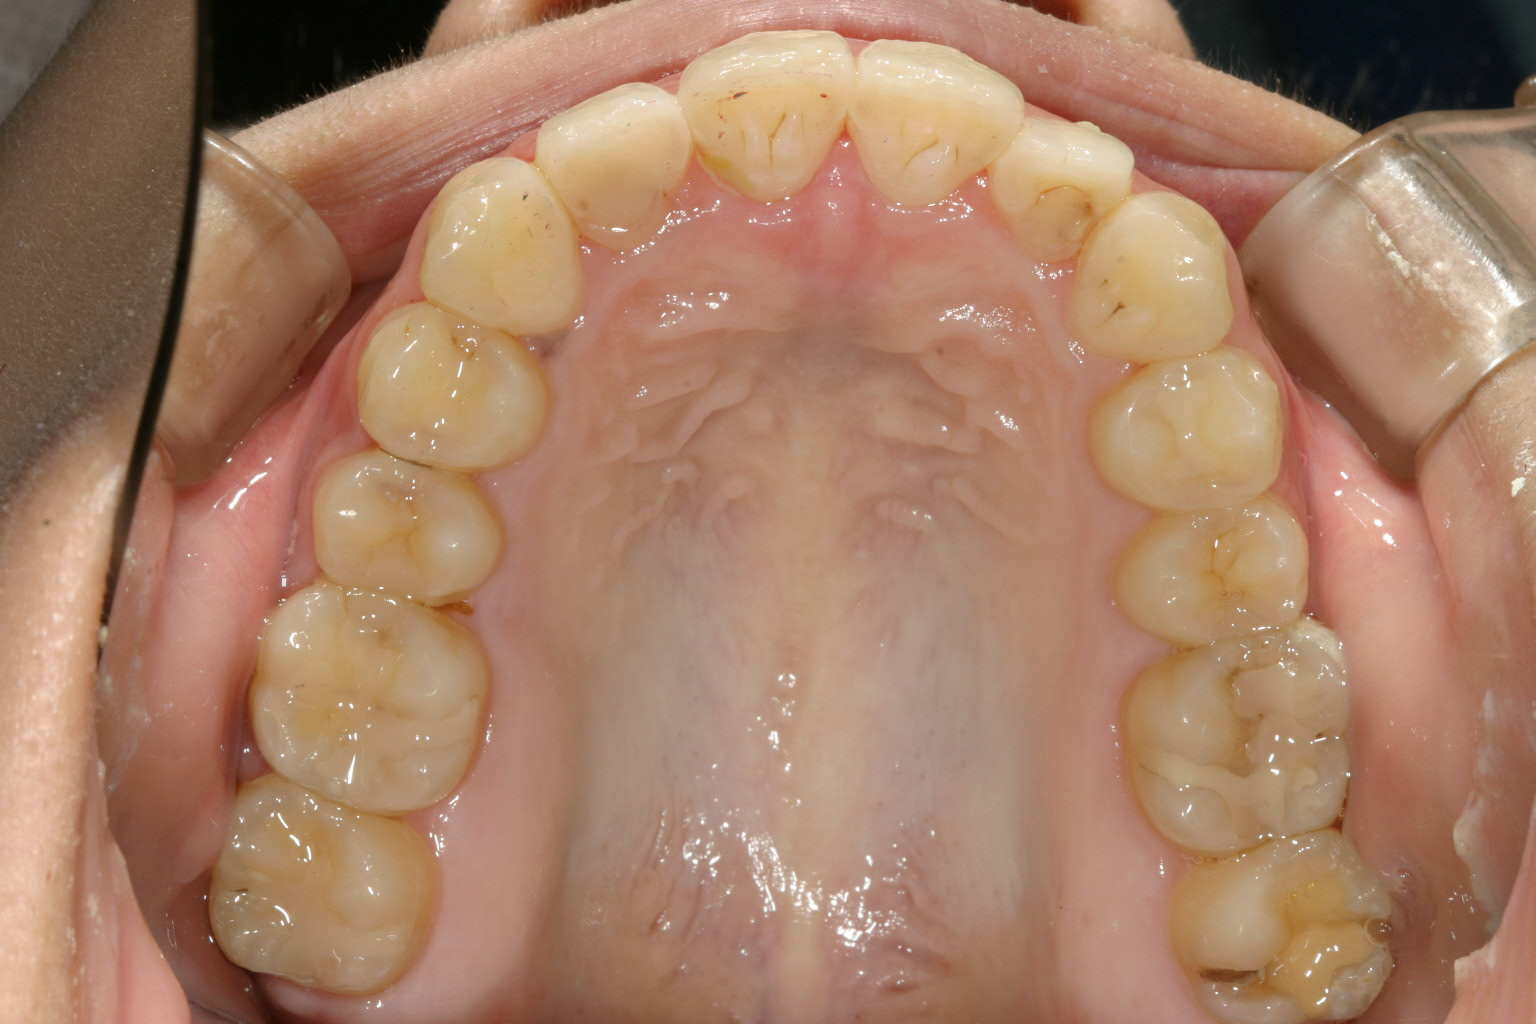

アーチを広げ、IPR(歯と歯の隙間を削る)を加え 出っ歯を改善しました。

下顎も上顎と同じ様にアーチ拡大とIPRです。

今回のケースは上下顎前突の為インビザラインによるアーチフォームの拡大とIPR(歯と歯の間を少し削る事)により抜歯せずともここまで改善しました。